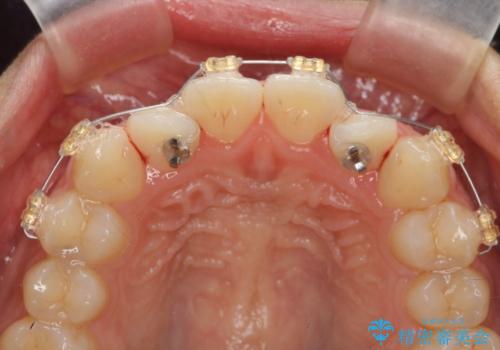

インビザラインによる矯正治療を行いますが、クロスバイトの改善をワイヤー部分矯正で事前に行うことにより治療期間の短縮する治療計画を立案します。

上下すれ違った噛み合わせはマウスピースでは改善に時間がかかり、またねじれが残ってしまうことも多々見られます。

マウスピース矯正を行う前に、これらの症状の改善の得意なワイヤー部分矯正を行うことで治療期間を短縮し、確実にすれ違いを改善することができます。